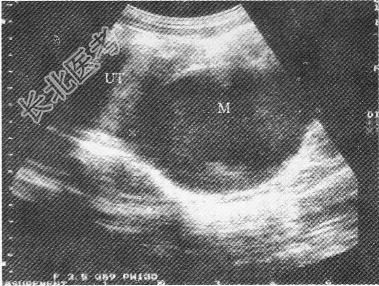

- 单项选择题女性,15岁, 周期性下腹部疼痛伴排尿困难;月经未来潮; 超声检查如图所示,最可能的诊断为

A、处女膜闭锁

B、子宫内膜癌宫腔积液

C、异位妊娠

D、宫颈囊肿

E、子宫肌瘤